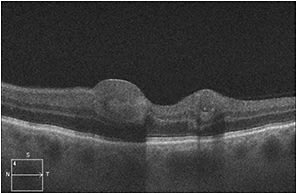

Fluorescein angiography demonstrated numerous punctate areas of hypofluorescence, consistent with blockage from the intraretinal hemorrhages (Figure 2). Spectral-domain OCT scans of the macula showed lesions within the inner retina corresponding to intraretinal hemorrhages but an otherwise unremarkable outer retina with an intact inner segment/outer segment junction and retinal pigment epithelium layer (Figure 3).

Figure 3. At presentation, SD-OCT of the left eye showed lesions corresponding to the intraretinal hemorrhage with shadowing but an otherwise intact outer retina and RPE.